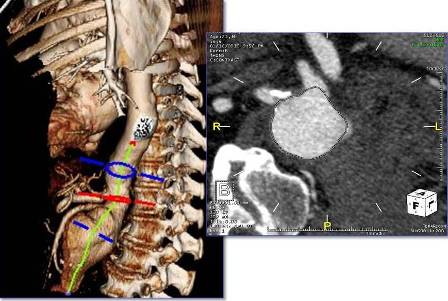

Using the most advanced, three-dimensional reconstruction

software, a custom-made endograft is planned and designed

for your patient’s specific anatomy.

For complex aneurysms (those aneurysms which include portions of the aorta with branch arteries that supply organs such as the kidneys and intestines), a special type of repair is required to preserve flow to these branch arteries: a fenestrated endograft, with special holes placed in the endograft at the precise location in which these branches arise. The fenestrated endograft is designed specifically to fit each patient’s particular anatomy; this is possible through the use of sophisticated imaging software that allows Dr Schanzer and his team to manipulate the CT images obtained of the patient’s aorta and branch arteries.

The fenestrated endograft, designed specifically for the particular patient, is then positioned inside the aorta from within the blood vessels in the groin; this allows for the aorta to be “re-lined”, with the holes positioned precisely to allow blood to continue to flow into the branch arteries, while blood flow no longer fills the aneurysm sac.

Some of the intraoperative techniques that facilitate this approach include the use of a state-of-the-art hybrid operating room. A CT scan is performed right in the OR; these images are merged with the preoperative CT scan images using “fusion” technology. This technology enhances the safety of the procedure by allowing Dr Schanzer and his team to minimize the amount of radiation and contrast dye that is used in the procedure.